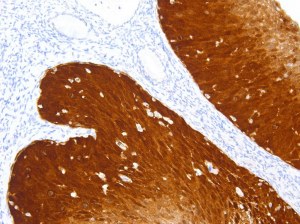

Der SarcomaFusion-Test erkennt Fusionstranskripte in Sarkomen. Diese Transkripte, die mit bestimmten Subtypen und gezielten Behandlungen assoziiert sind, sind für die Patientenversorgung von entscheidender Bedeutung. Durch den Einsatz der patentierten ligationsabhängigen PCR-Technologie vereinfacht der Test die Diagnostik und verbessert unser Verständnis der Sarkombiologie. Dank seines schnellen Protokolls und seiner Robustheit ist er ein wertvolles Instrument in der Onkologie.